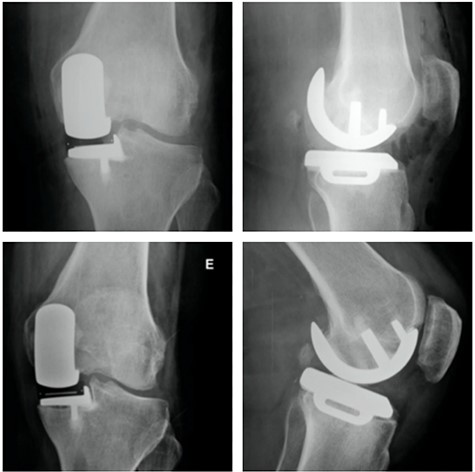

Coronal (A) and sagittal (B) T2 MRI—left knee—showing severe MP SIFK; Anterior (C) and lateral view (D) X-ray images of immediate postoperative period (medial UKA); Anterior (E) and lateral view (F) X-ray images with 3 months of follow-up with tibial component loosening.